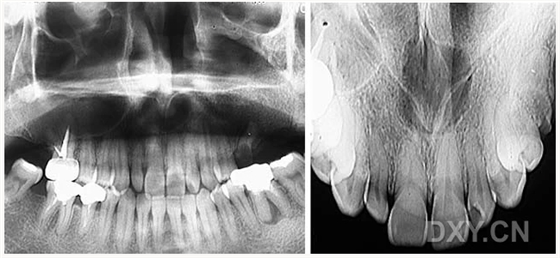

牙源性鈣化囊腫

牙瘤!

牙源性鈣化囊腫    牙瘤!